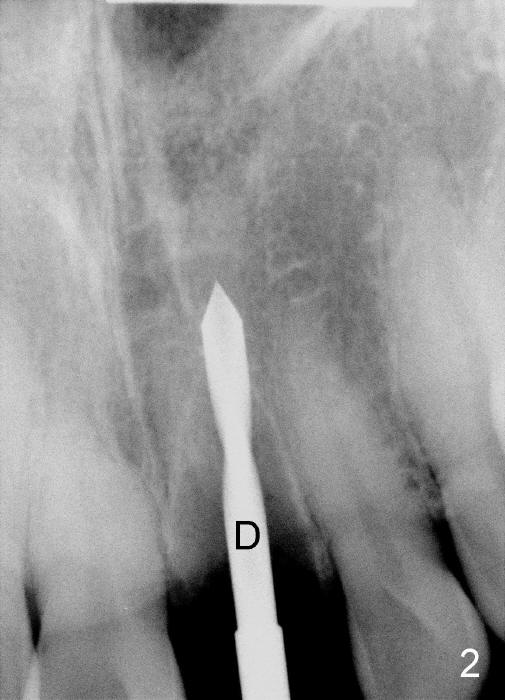

The upper right central incisor (Fig.1: #9) fractures subgingivally due to trauma for a 40-year-old man. The incisive canal is large (I) and close to the root of the central incisor. After extraction, the osteotomy (Fig.3b, 4: O) is made with 2 mm pilot drill (Fig.2: D) on the lingual wall (Fig.3a: L) of the socket (Fig.3a: S). To push the incisive canal mesially, the osteotomy is enlarged by 3.5x21 mm and 4x21 mm tapered osteotomes (Fig.5,6: O). Due to the lingual slope (Fig.7a arrow), the osteotome (blue outline) starts to deviate bucally. To reduce this tendency, the coronal portion of the lingual slope is removed (Fig.7b: yellow circle). The final implant (4.5x20 mm) is able to be placed as lingually as possible (Fig.7c, 8).

Bone expansion allows the implant (Fig.9 I) to have primary stability (insertion torque between 50 and 60 Ncm), since the cortex of the incisive canal is apparently intact. Allograft is placed in the labial gap (Fig.10, 11 *) following installation of the abutment (A). Finally an immediate provisional (Fig.10,12 P) is cemented. Fig.13,14 are taken 8 days postop. The patient returns 3 months postop (Fig.15,16). Osteointegration appears to have occurred (Fig.15 arrowheads) and is more obvious 9 months postop (Fig.17).